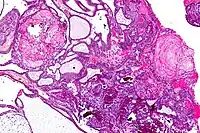

Very low magnification micrograph of an adamantinomatous craniopharyngioma. HPS stain.

On macroscopic examination, craniopharyngiomas are cystic or partially cystic with solid areas. On light microscopy, the cysts are seen to be lined by stratified squamous epithelium. Keratin pearls may also be seen. The cysts are usually filled with a yellow, viscous fluid rich in cholesterol crystals. Of a long list of possible symptoms, the most common presentations include headaches, growth failure, and bitemporal hemianopsia.